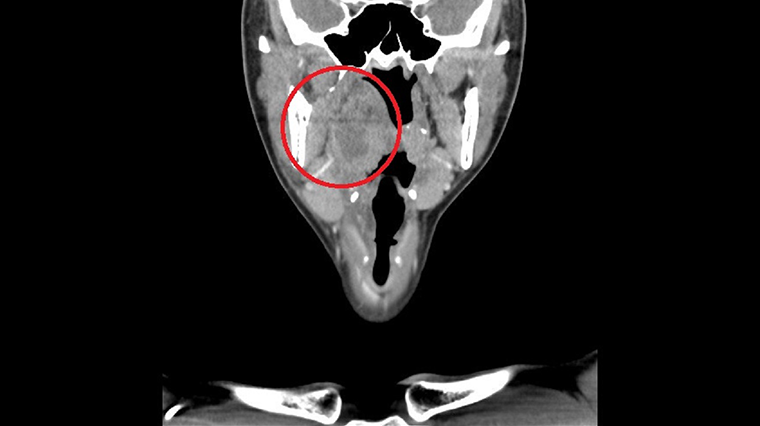

▲影像檢查結果顯示患者的扁桃腺及周圍組織明顯腫大。(圖/亞洲大學附屬醫院提供)

於是先安排理學檢查,發現病患張口困難,且疼痛以單側為主,內視鏡檢查右側扁桃腺已有化膿情形,扁桃腺周圍組織如軟顎、側咽壁都嚴重腫脹,連懸壅垂都被推移至對側,因此確診為「右側扁桃腺周圍濃瘍」,抽血檢查結果也有敗血症跡象,於是安排病人住院接受膿瘍切開引流手術,經給予抗生素及輸液治療後,順利在5天後康復出院。